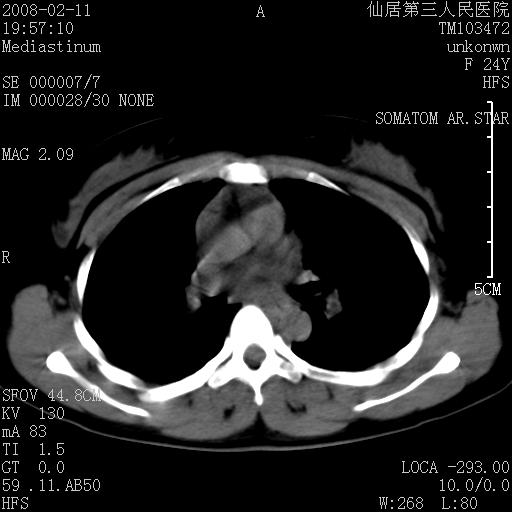

以下是引用zjzjr在2008-2-12 14:32:00的发言:[br]胸腺大点,是不是胸腺瘤或胸腺增生